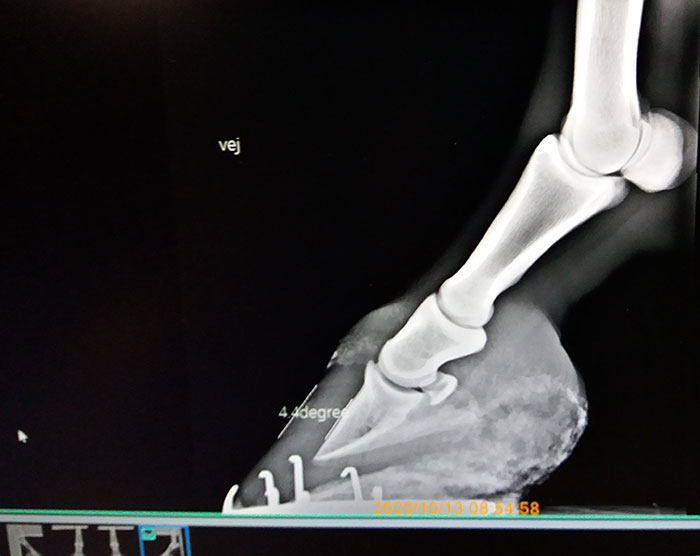

Junnuosasto oli paikalla ensisijaisesti tapaamassa samaa kengittäjää kuin emänsä, vaikkakin edelleen ilman varsinaista kengitysosuutta. Koska satuimme nyt olemaan jo laitteiden äärellä, Albertin kavioista napattiin needellisellä säteilytyskerralla käsittämättömästi ottamatta jääneet kuvat. Ja hyvä, että otettiin.

Kolme kaviota oli ihan ok, mutta vasemmassa takakaviossa oli kavioluu aivan ns. keturallaan. Kyseisessä kavioluussa näkyi myös "linja", joka eläinlääkärin arvion mukaan oli todennäköisesti hiusmurtuma.

Murtuma, siinäpä sana, jota en tältä reissulta odottanut. Onneksi linja oli sellaisessa paikassa, että eläinlääkäri arveli sen korjaantuvan ilman erityisiä elämisen rajoitteita, kun samalla kertaa saatiin helpotettua kavioluun virheasennon luomaa painetta uudella uljaalla vuolulla. Olisikin ollut vähän liikaa yhdelle 3-vuotiaalle, että juuri kun se on kuumetaudin jälkeen päässyt takaisin bändiin, joutuisi taas soolouralle.